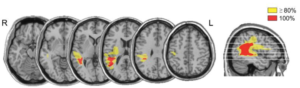

対象となったのは右半球損傷を生じ、半側空間無視症状を生じた患者9名と健常対照群18名で、損傷領域は主に頭頂葉後部および側頭頭頂接合部(TPJ)になります。

これらの実験の結果から、頭頂葉後部および側頭頭頂接合部を損傷した左半側空間無視患者においては

・ボトムアップ的な注意もトップダウン的な注意も共に同じように障害されうる

・視界に勾配をかけることで視線の向きやすさを調整することができる

ということが述べられています。